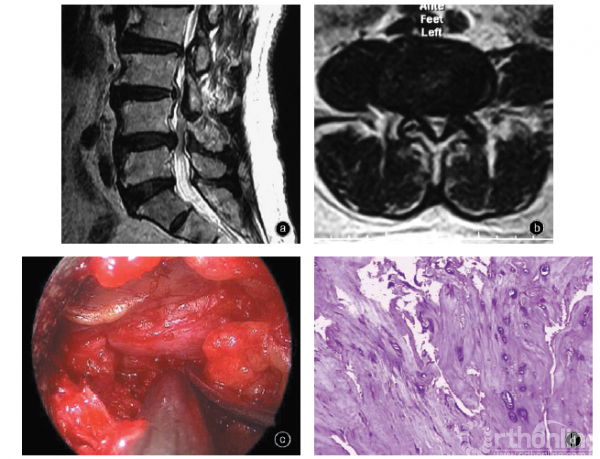

图2 男,71岁,椎间盘退变突出 a 矢状面MRIT2WI示L4-5椎间盘突出 b 横断面MRI T2WI示关节突关节和黄韧带增生肥厚,椎管侧方狭窄 c 后路脊柱内镜术中见突出物质地硬韧(器械所指),切开后无成块的破碎椎间盘组织 d 突出的椎间盘组织在光镜下可见纤维软骨基质退变,无新生血管形成 HE染色×200

退变突出型为退行性变引起的椎间盘弥漫或局限性突出,相当于MacNab分类和Spengler分类中的突出(protrusion)、周秉文分类中的突起型、AAOS & ISSLS 分类中的退变、膨出和突出型,类似概念还有bulge、displacement、hardherniation。此型椎间盘突出表现为病变部位质地硬、无弹性、触压时多不诱发疼痛,突出部分是完整椎间盘的一部分,切开表层组织无破碎的椎间盘,不能摘除成块的椎间盘组织,切除困难(图2)。突出病变部压力基本正常,与髓核无明显差异。术中椎间盘造影时弥漫充盈、扁平扩大,或呈多支分散状而没有中央阴影,提示纤维环多发撕裂。

(一)病理学改变

光镜下髓核和纤维环结构相对完整,髓核缩小、组织致密,纤维环增厚,移行区界限不明显,软骨基质增生,可见较多的软骨样陷窝细胞增殖,胶原纤维异常增生,排列致密且无序(图2)。

电镜下呈以组织增生为主的征象,胶原纤维大量增生、致密、排列紊乱,细胞合成活跃。胶原纤维异常增生反应与患者年龄、脊柱退变及失稳状况相关,是机体为维持脊柱稳定而产生的适应性改变。

免疫组织化学检查可见髓核退变、软骨基质及纤维环增生,软骨细胞Ⅰ型胶原染色阳性。无T淋巴细胞浸润,偶见少量巨噬细胞(CD68和CD45RO阳性细胞),但CD4和CD8免疫染色一般无阳性细胞。IgG和IgM免疫荧光反应阴性,外周血IgG、IgM水平低于损伤疝出型患者。椎间盘退变可能是多种因素协同作用的结果,通过细胞膜和细胞内信号传导通路传递到细胞核、影响基因表达,进而影响蛋白多糖和胶原蛋白合成与降解的动态平衡、细胞调亡和组织退变。

因此,退变突出型腰椎间盘突出的病理实质是以退变和增生反应为主的病理过程。